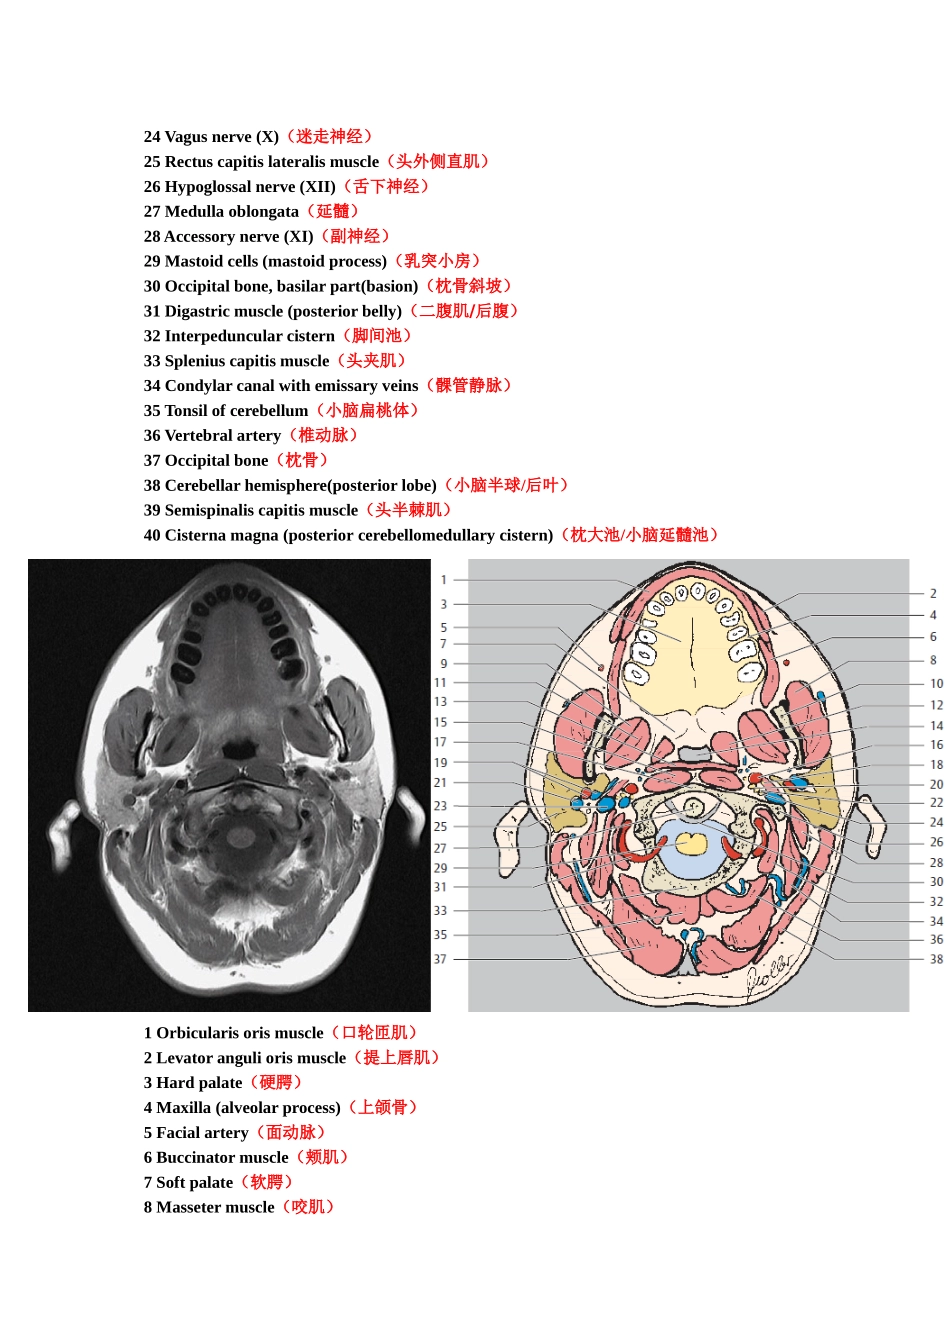

1Orbicularisorismuscle(口轮匝肌)2Levatorlabiisuperiorismuscle(提上唇肌)3Maxilla(palatineprocess)andincisivecanal(上颌骨和门齿管)4Levatoranguliorismuscle(提口角肌)5Maxillarysinus(上颌窦)6Majorzygomaticusmuscle(颧大肌)7Softpalate(软腭)8Massetermuscle(咬肌)9Nasopharynx(鼻咽)10Medialpterygoidmuscle(翼内肌)11Temporalmuscle(颞肌)12Tensorvelipalatinimuscle(腭帆张肌)13Lateralpterygoidmuscle(翼外肌)14Mandibularnerve(V3)(下颌神经)15Pharyngotympanictube(auditorytube)(咽鼓管)(toruslevatorius)(提肌圆枕/咽鼓管圆枕)16Maxillaryartery(上颌动脉)17Longuscapitismuscle(头长肌)18Retromandibularvein(下颌后静脉)19Ramusofmandible(下颌支)20Levatorvelipalatinimuscle(腭帆提肌)21Glossopharyngealnerve(IX)(舌咽神经)22Occipitalbone,basilarpart(basion)(枕骨/枕骨斜坡)23Internalcarotidartery(颈内动脉)24Parotidgland(腮腺)25Vagusnerve(X)(迷走神经)26Internaljugularvein(颈内静脉)(superiorbulb)(颈静脉上球)27Hypoglossalnerve(XII)(舌下神经)28Vertebralartery(椎动脉)29Interpeduncularcistern(脚间池)30Sigmoidsinus(乙状窦)31Mastoidcells(乳突小房)32Medullaoblongata(延髓)33Vermis(小脑蚓部)34Tonsilofcerebellum(小脑扁桃体)35Occipitalbone(枕骨)36Cerebellarhemisphere(小脑半球)(posteriorlobe)(后叶)37Cisternamagna(枕大池)(posteriorcerebellomedullarycistern)(小脑延髓池)38Semispinaliscapitismuscle(头半棘肌)1Orbicularisorismuscle(口轮匝肌)2Levatoranguliorismuscle(提上唇肌)3Maxilla(alveolarprocess)(上颌骨)4Hardpalate(硬腭)5Buccinatormuscle(颊肌)6Zygomaticusmuscle(颧肌)7Softpalate(软额)8Facialartery(面动脉)9Lateralpterygoidmuscle(翼外肌)10Massetermuscle(咬肌)11Medialpterygoidmuscle(翼内肌)12Temporalmuscle(颞肌)13Levatorvelipalatinimuscle(腭帆提肌)14Ramusofmandible(下颌支)15Spleniuscapitismuscle(头夹肌)16Tensorvelipalatinimuscle(腭帆张肌)17Longuscapitismuscle(头长肌)18Nasopharynx(鼻咽)19Anteriorarchofatlas(寰椎前弓)20Internalcarotidartery(颈内动脉)21Internaljugularvein(颈内静脉)22Parotidgland(腮腺)23Retromandibularvein(下颌后静脉)24Vagusnerve(X)(迷走神经)25Rectuscapitislateralismuscle(头外侧直肌)26Hypoglossalnerve(XII)(舌下神经)27Medullaoblongata(延髓)28Accessorynerve(XI)(副神经)29Mastoidcells(mastoidprocess)(乳突小房)30Occipitalbone,basilarpart(basion)(枕骨斜坡)31Digastricmuscle(posteriorbelly)(二腹肌/后腹)32Interpeduncularcistern(脚间池)33Spleniuscapitismuscle(头夹肌)34Condylarcanalwithemissaryveins(髁管静脉)35Tonsilofcerebellum(小脑扁桃体)36Vertebralartery(椎动脉)37Occipitalbone(枕骨)38Cerebellarhemisphere(posteriorlobe)(小脑半球/后叶)39Semispinaliscapitismuscle(头半棘肌)40Cisternamagna(posteriorcerebellomedullarycistern)(枕大池/小脑延髓池)1Orbicularisorismuscle(口轮匝肌)2Levatoranguliorismuscle(提上唇肌)3Hardpalate(硬腭)4Maxilla(alveolarprocess)(上颌骨)5Facialartery(面动脉)6Buccinatormuscle(颊肌)7Softpalate(软腭)8Massetermuscle(咬肌)9Lateralpterygoidmuscle(翼外肌)10Ramusofmandible(下颌支)11Medialpterygoidmuscle(翼内肌)12Tensorvelipalatinimuscle(腭帆张肌)13Superiorconstrictormuscleofpharynx(咽上缩肌)14Pharynx(鼻咽)15Longuscapitismuscle(头长肌)16Internalcarotidartery(颈内动脉)17Atlas(anteriorarch)(寰椎前弓)18Glossopharyngealnerve(IX)(舌咽神经)19Maxillaryarteryandvein(上颌动脉与静脉)20Vagusnerve(X)(迷走神经)21Retromandibularvein(下颌后...